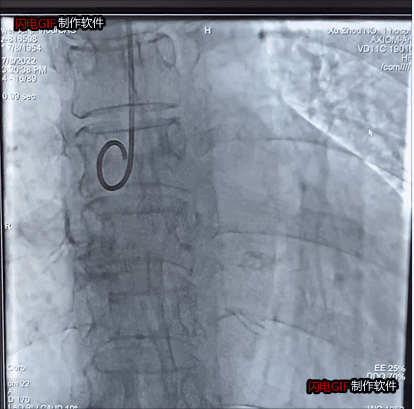

瓣膜植入前主動(dòng)脈瓣大量反流

瓣膜植入后反流完全消失

整個(gè)手術(shù)過程僅1小時(shí),瓣膜釋放后主動(dòng)脈瓣反流完全消失,舒張壓迅速由14上升到60mmHg左右。目前患者已順利康復(fù)出院。